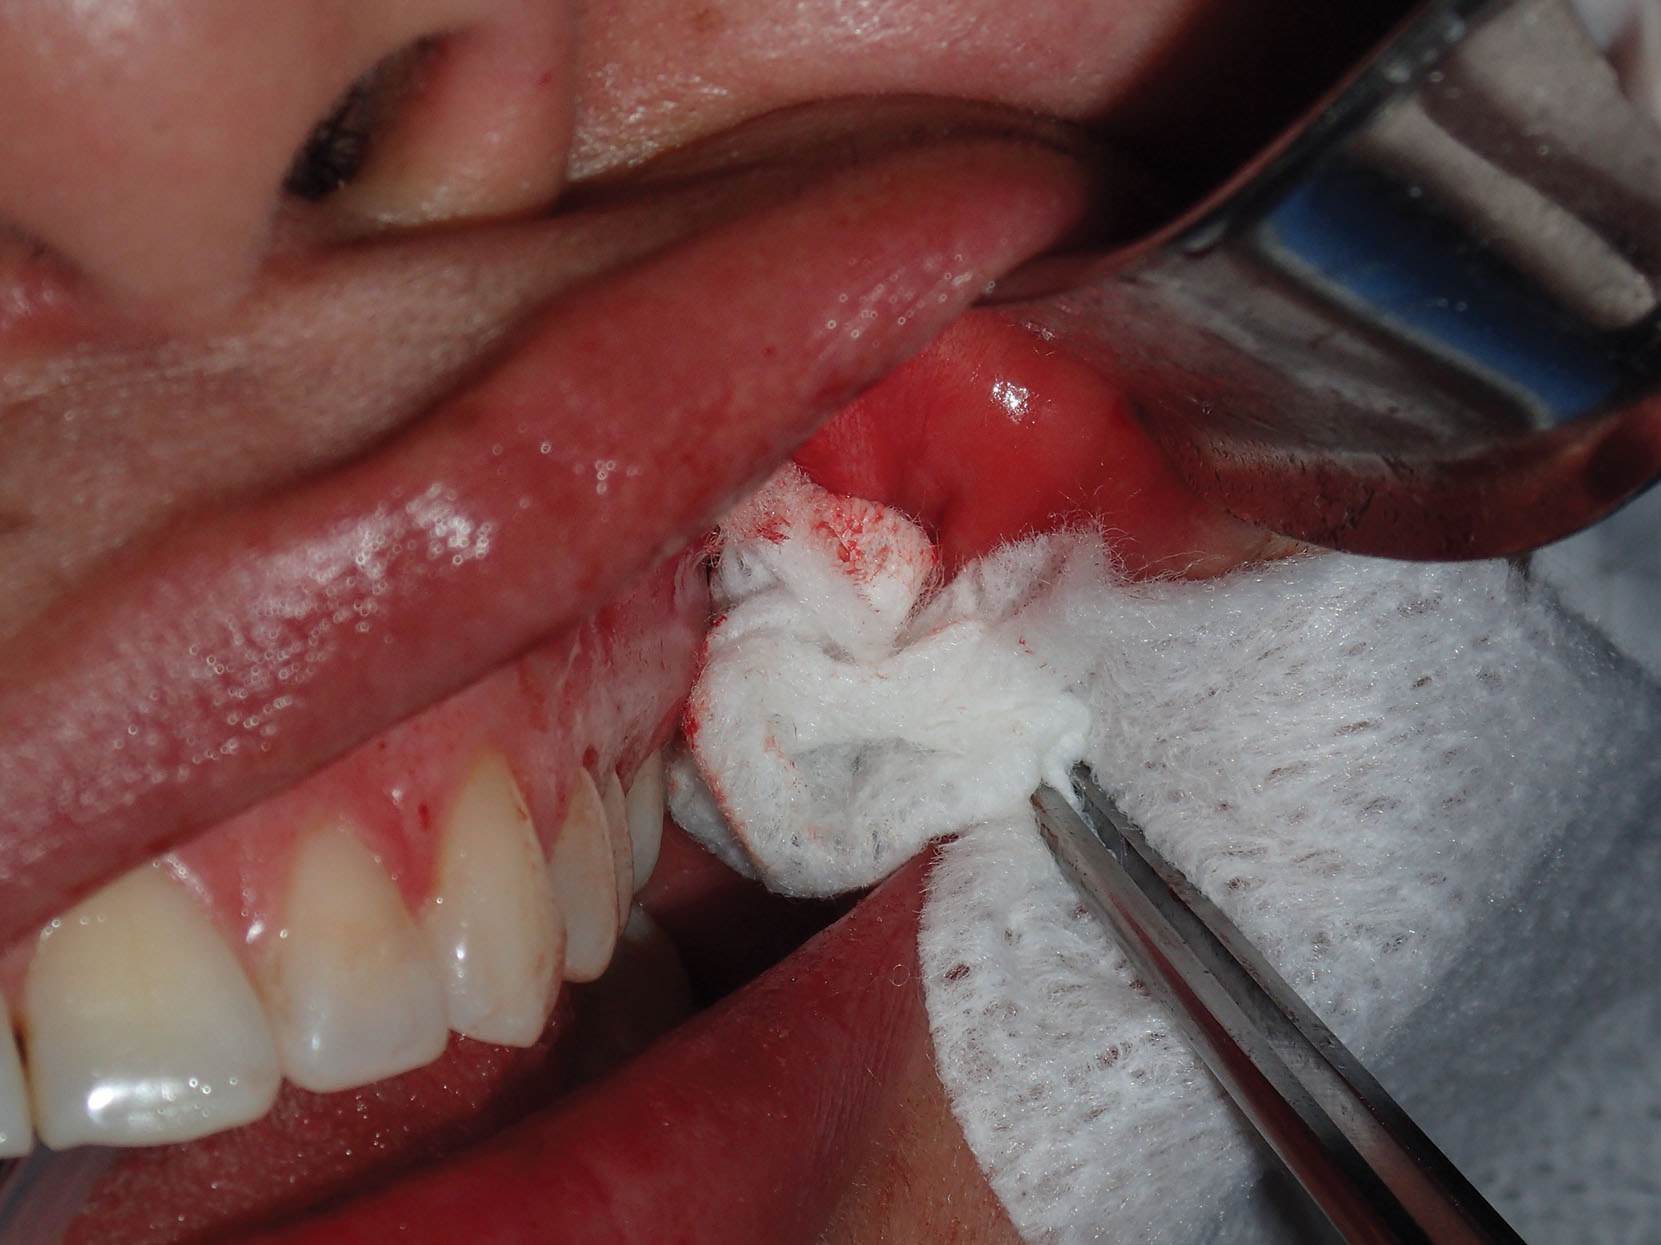

After sufficient fat is removed, the surgical site is checked for hemostasis. The buccinator muscle at the incision site is a frequent source of bleeding and can contribute to a hematoma. If active bleeding is encountered deeper in the wound, cauterization must be carefully addressed as facial nerve branches can be in the proximity as they traverse the masseter muscle. Packing the wound with gauze can also assist in hemostasis. Wound closure is performed with one or two 4-0 gut sutures.

Postsurgically, gauze packs are placed between the cheeks, and a compressive dressing is placed for 24 hours. This dual-layer compression assists in eliminating dead space and may assist in control of bleeding and swelling ( Fig. 15.25 ).